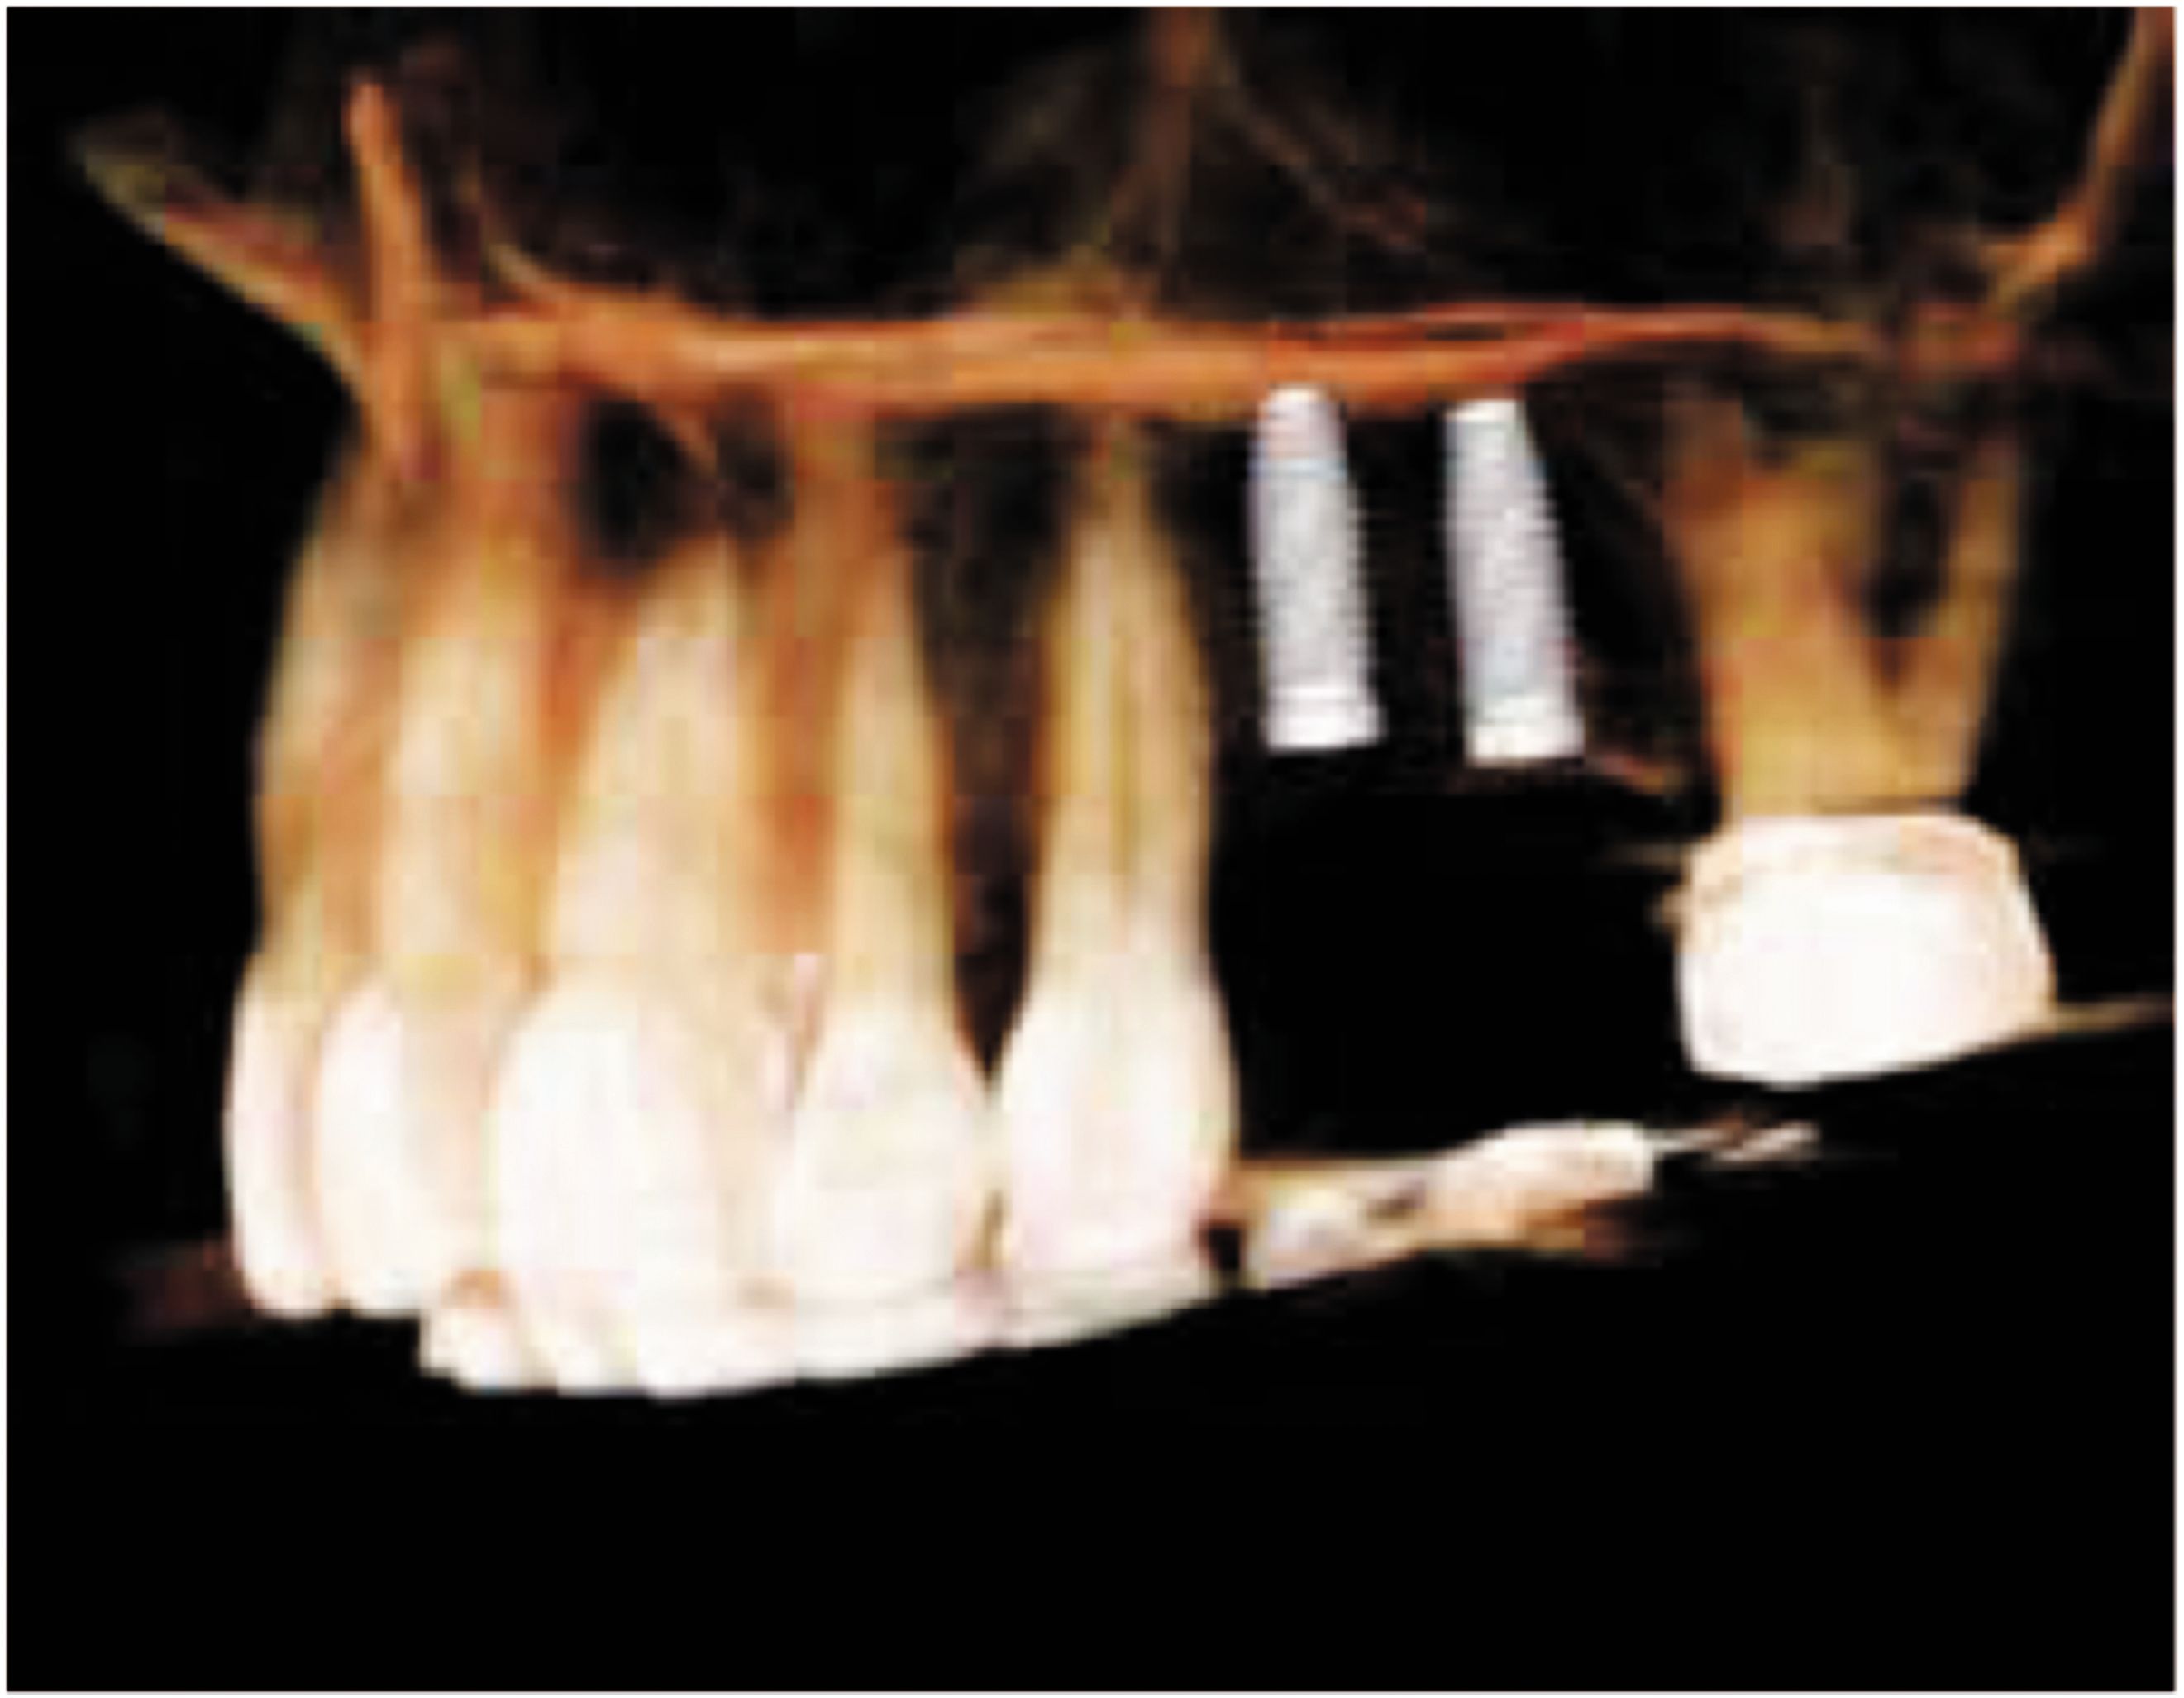

OP300 Maxio scans provide clinical-rich information to assist clinicians in the treatment planning process. The feature-rich 3D software enhances the data and gives you full control to design crowns, abutments and implants right from your Cone Beam 3D scan for fast, accurate treatment planning and predictable results. In just three simple steps, the software allows you to implant plan from the crown down:

1. OP300 Maxio software gives the ability to adjust and size the implant directly within the 3D rendering making the entire implant selection and positioning process a breeze.

2. Virtually add crowns from the restoration library and plan them within the 3D scan. With a few clicks of the mouse, you can also design your restoration to meet the functional requirements of your treatment plan.

3. Complete the design by adding the abutment and make any final adjustments quickly and accurately. This will allow you to refine and verify the implant selection and placement in respect to the restoration.

Once your design is complete, just select to transfer the case to the cloud server to have high-quality surgical guides made by Anatomage. With a fast turnaround, the guides will be produced in California at a flat fee independent from the number of implants or the complexity of the design.